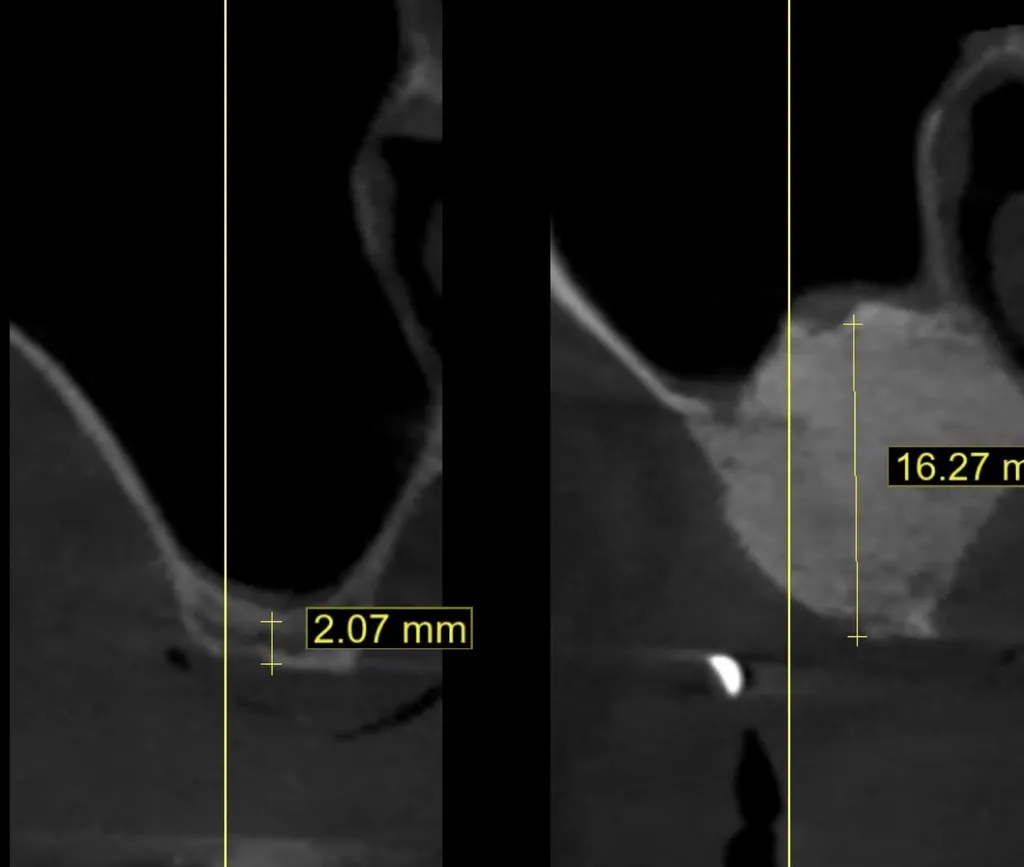

Cette technique spécifique est indispensable lorsque l'on veut poser des implants dentaires dans le secteur postérieur du maxillaire supérieur, où se trouvent les sinus maxillaires.

• Le Problème : Après la perte des dents postérieures, le plancher sinusal a tendance à descendre et l'os résiduel est insuffisant en hauteur.

• La Solution : Le sinus lift (ou élévation du plancher sinusal) consiste à soulever délicatement la membrane qui tapisse le sinus (membrane de Schneider) et à combler l'espace créé avec un matériau de comblement osseux.

• Deux Techniques :

• Technique de Crête (Ostéotome) : Mini-invasive, par la crête gingivale, pour de petites augmentations.

• Technique Latérale : Via une fenêtre osseuse sur le côté du sinus, pour des augmentations plus importantes.

• Délai : La pose de l'implant peut être immédiate (si l'os résiduel est suffisant) ou différée de 6 à 9 mois après la greffe.

• L’Élévation de Sinus (Sinus Lift) : Spécifique aux molaires et prémolaires du haut, cette intervention est indispensable lorsque le sinus maxillaire s’est abaissé et qu’il ne reste que quelques millimètres d’os. En soulevant la membrane du sinus et en comblant l’espace avec de l’os, le chirurgien crée la hauteur nécessaire pour loger l’implant dans de bonnes conditions.